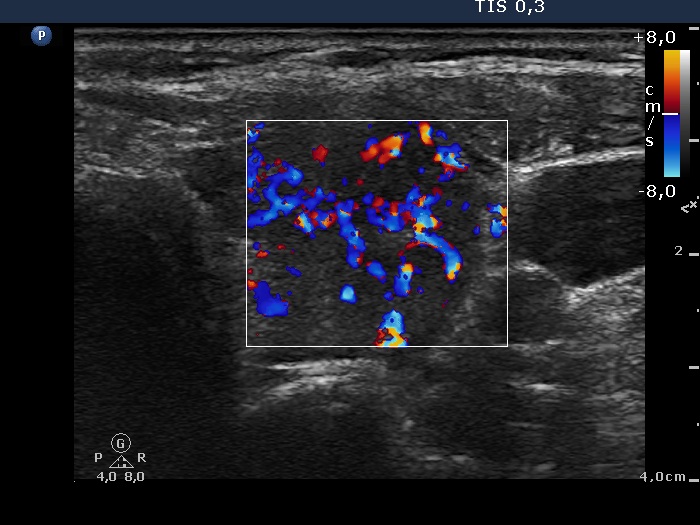

Lower part of the left lobe, transverse scan, color Doppler mode. The vascularization is increased.